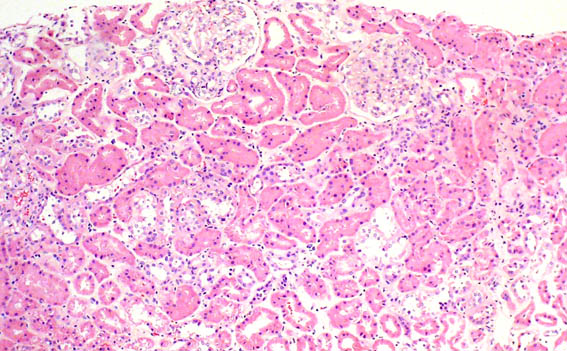

Figure 1. H&E, X100.